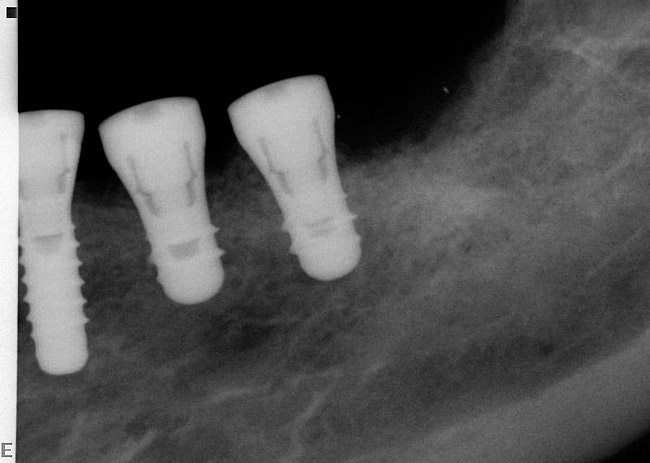

A surgical guide, based on the 3-dimensional implant locations is fabricated for use in conjunction with the selected implant manufacturer's guided surgery instrumentation (Figure 4). Using this template, safe implant positioning in all three dimensions is performed, avoiding trauma to vital anatomic structures respecting the restorative outcome prescribed prior to surgery (Figure 5 and Figure 6). Following 8 weeks of transmucosal healing time, standard restorative therapy is initiated (Figure 7).

Figure 5  Computer-guided implant placement.

Figure 5

Figure 6  Computer-guided implant placement.

Figure 6